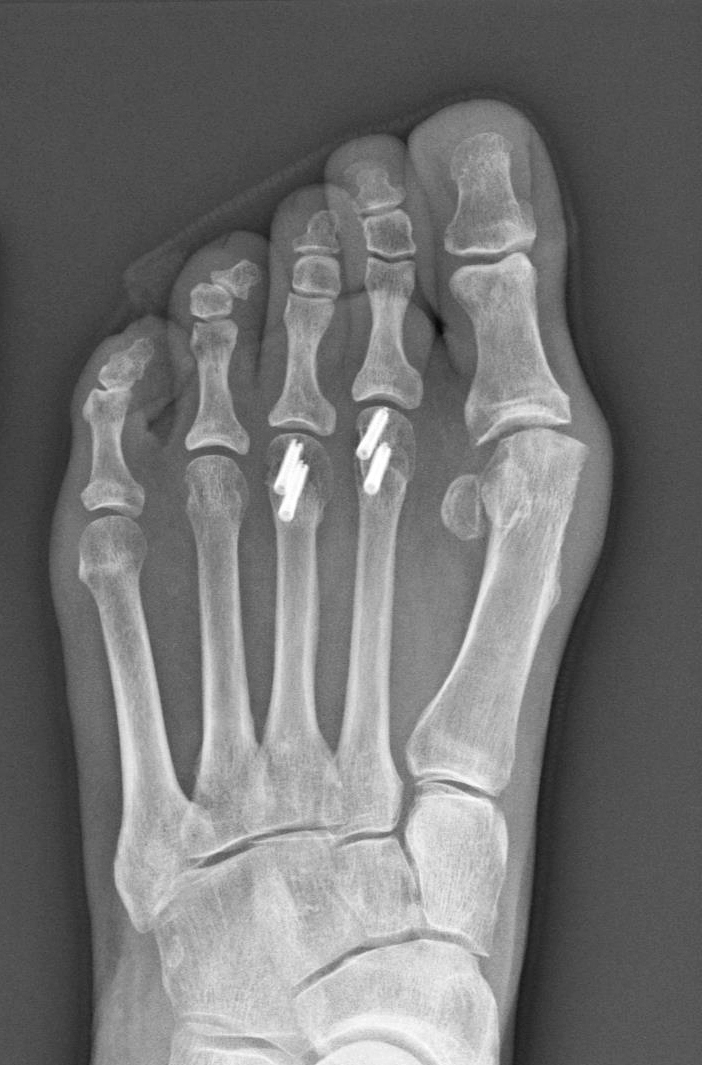

An X-ray of Sherry Young's foot shows the four implanted screws — each of which cost more than a high-end computer. (Courtesy of Sherry Young)